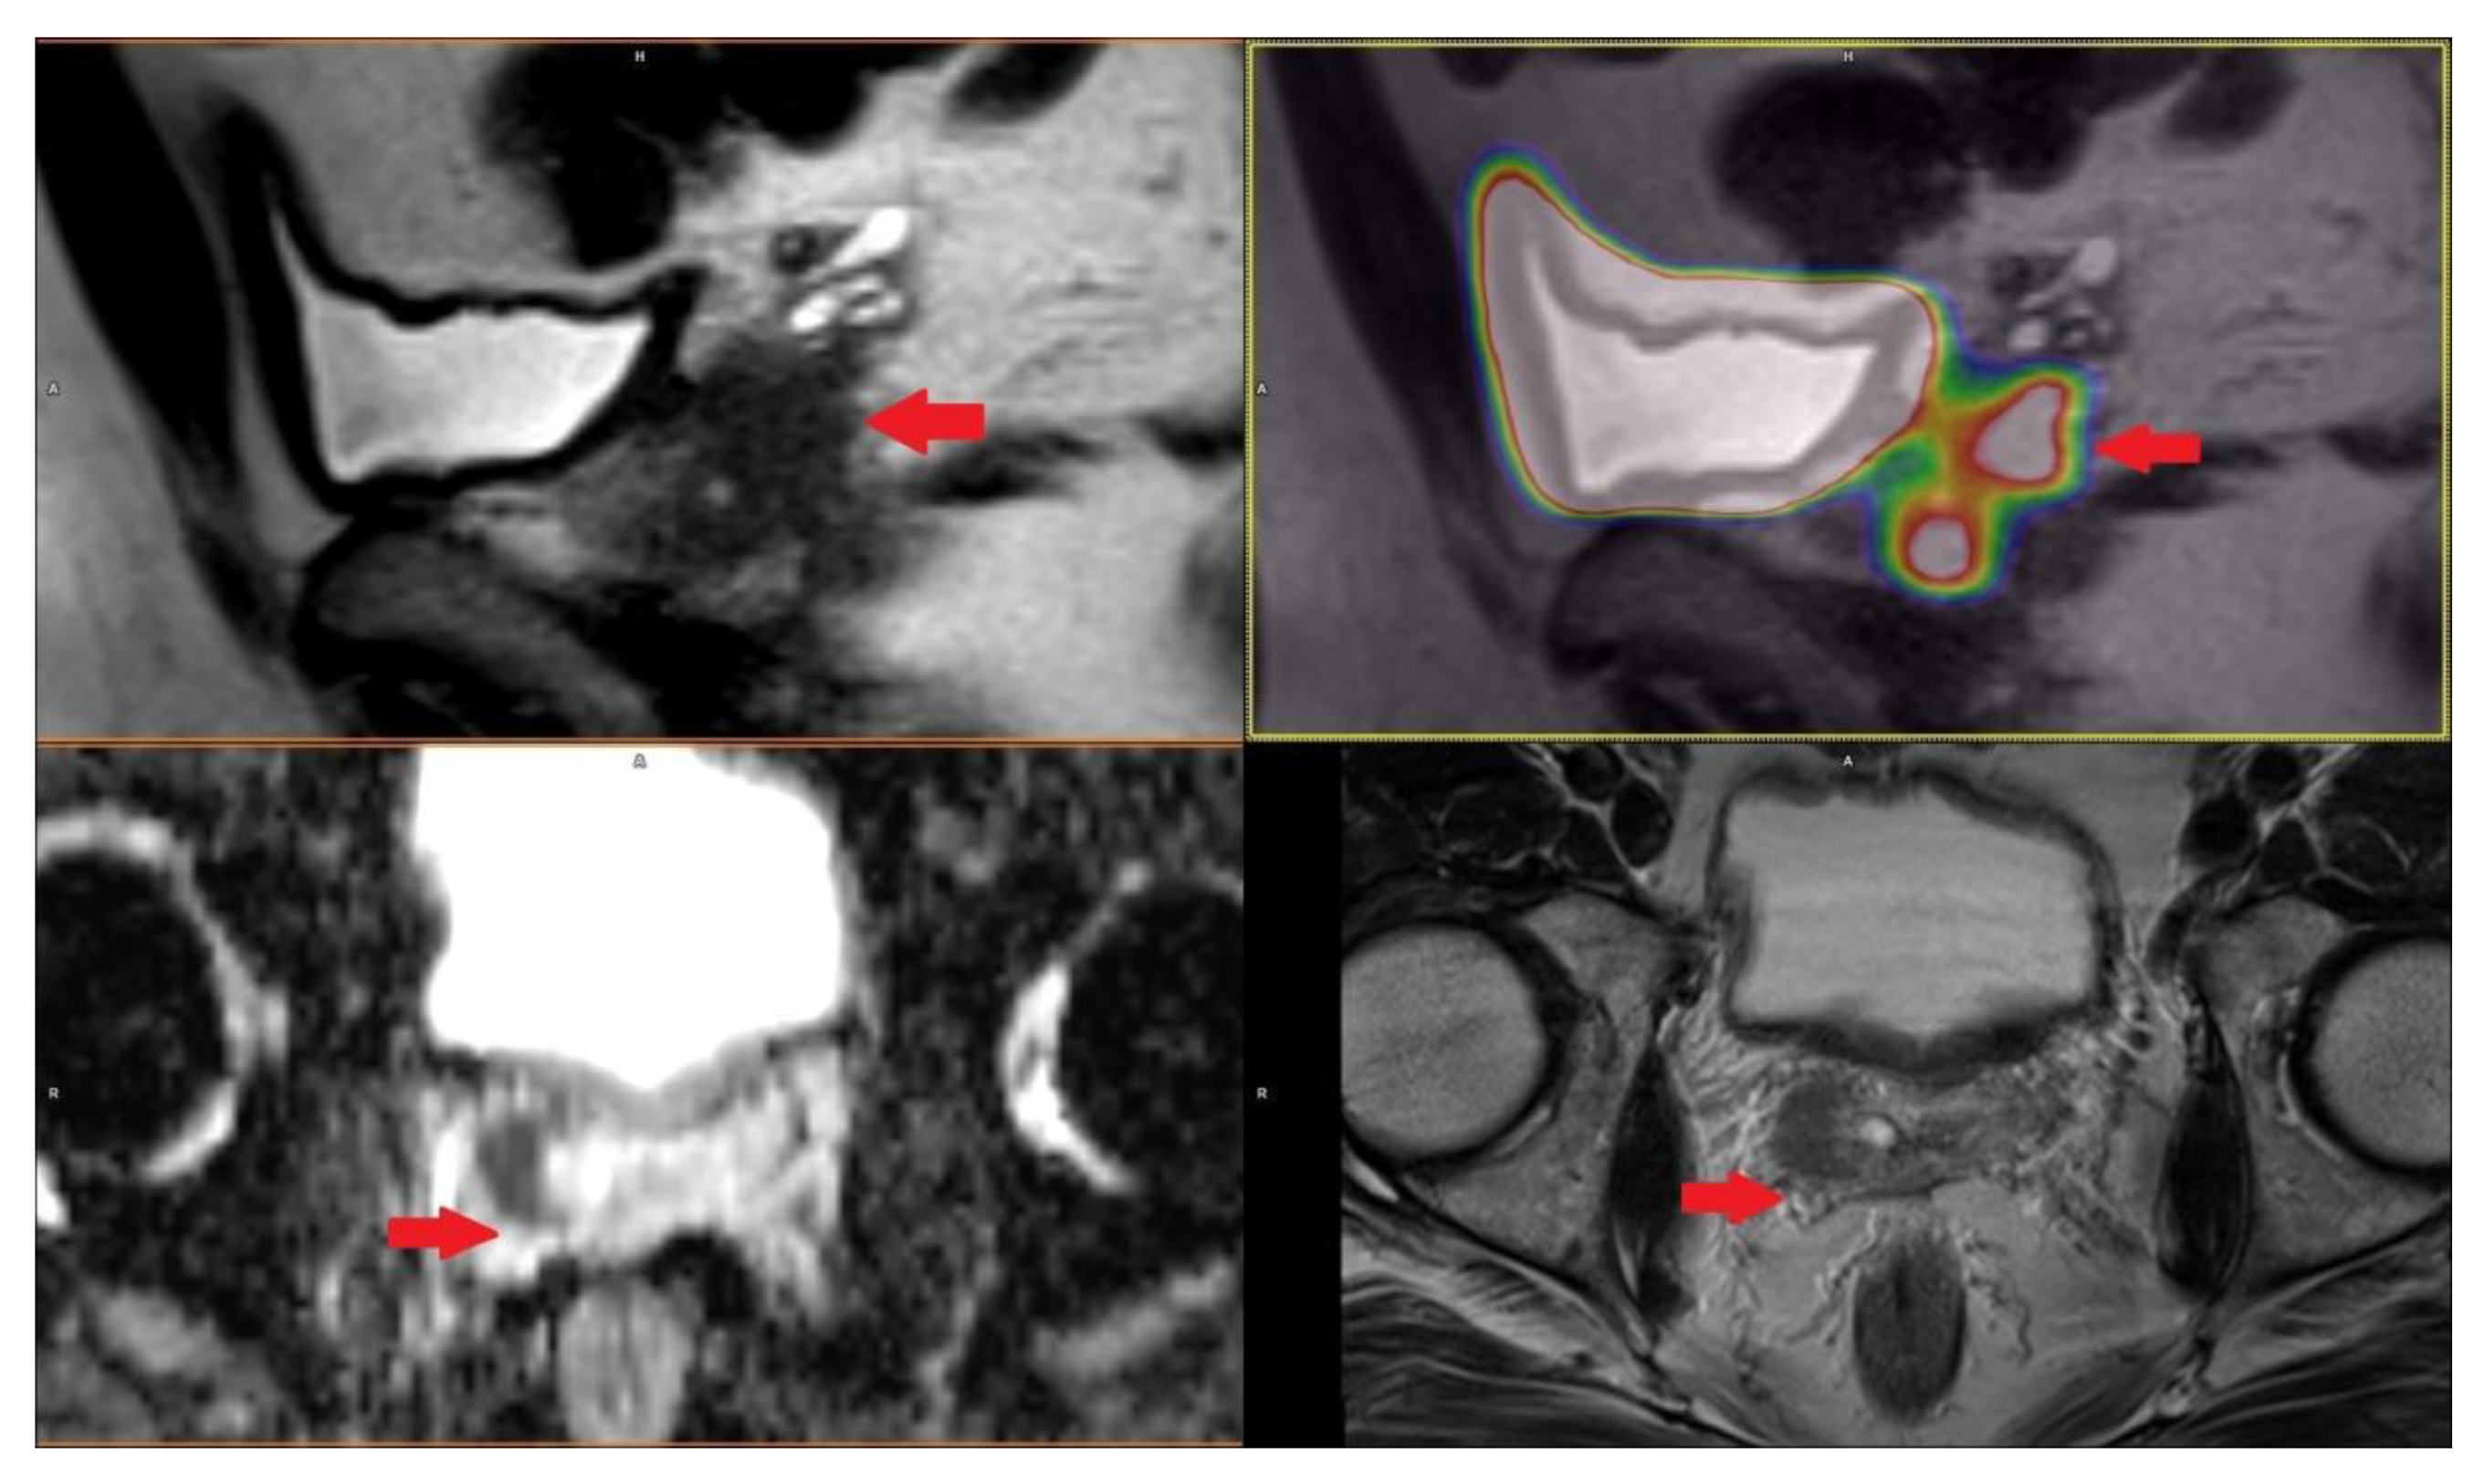

PET/CT with radiolabeled choline analogs is widely used in clinical practice for prostate cancer staging. 18F-fluoroethylcholine PET demonstrated higher accuracy than MRI for the detection of primary prostate cancer; specificity was however limited by choline uptake in benign lesions [15]. Since 2012, [18F]- and [68Ga]-labeled inhibitors of prostate-specific membrane antigen (PSMA) entered early clinical development for PET imaging of PCa and showed immediate promise for sensitive and specific identification of local and distant sites of disease [16,17]. Results from [68Ga]-PSMA-11 PET/MRI and PET/CT in Figure 2, Figure 3 and Figure 4. To summarize, according to the available systematic reviews and clinical trials, the sensitivity and specificity in primary staging of PCa using PSMA ligands is usually above 40% and over 85%, respectively. The impact on therapy planning was also investigated, performing PET/CT or, less frequently, PET/MRI using PSMA ligands, the therapeutic procedure changes in approximately 21% of patients in the primary staging [18,19].

Hybrid imaging using PET and MRI has been intentionally incorporated into the algorithm. MRI is perfect for the imaging of both the prostate, especially for targeted prostate biopsy, and for the detection of lymph node metastases. It has an irreplaceable role in preoperative lymph node staging. Having used the [68Ga]-PSMA-11 as the latest radiotracer with very promising results, we believe that thus performed staging is highly specialized and yields the best results. [68Ga]-labelled PSMA ligand could be superior to choline tracers in its ability to obtain high contrast. PSMA tracer can detect lesions characteristic of PCa with improved contrast when compared to the standard [18F]-fluoromethylcholine, especially at low PSA levels. A significant advantage of [68Ga]-PSMA-11 is that lesions characteristic of lymph node metastases are frequently presented in very high contrast when compared to choline. The superior contrast in [68Ga]-PSMA-11 has also been demonstrated in most skeletal metastases [28].

Figure 4. Patient with multiple bones metastases in prostate cancer GS 8 (4 + 4) iPSA 45.33 PHI 176.8 in [68Ga]-PSMA-11 PET/CT.

Life 11 00324 g004